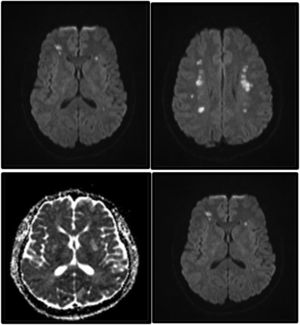

Laboratory analyses for rheumatic and haematological diseases ruled out blood clotting disorders. A contrast brain MRI scan revealed multiple subcortical lesions compatible with acute ischaemic lesions in both hemispheres, predominantly at the level of the centrum semiovale (Fig. 1). Hyperintense lesions were found in the subcortical white matter of both temporal poles (Fig. 2). CT angiography of the brain and neck detected no abnormalities. Transthoracic echocardiography with microbubbles yielded normal results. Brain angiography and positron emission tomography ruled out vasculitis. The patient received treatment with acetylsalicylic acid dosed at 100 mg/day and required feeding with a nasoduodenal tube due to dysphagia. Imaging findings were suggestive of CADASIL; sequencing of the NOTCH3 gene revealed heterozygosity for a pathogenic variant associated with the disease. The patient's neurological symptoms progressed favourably. At discharge, the patients scored 1 on the National Institutes of Health Stroke Scale due to mild dysarthria. At 3 months from symptom onset, he scored 1 point on the modified Rankin Scale.